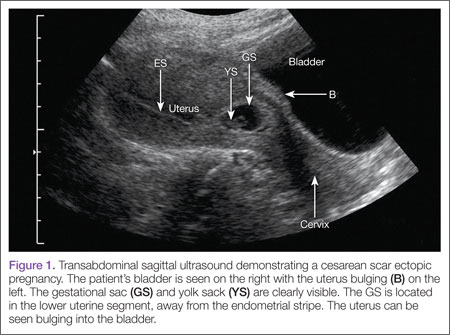

Regardless of one’s clinical suspicion, the diagnosis is made (or ruled out) through ultrasound. Uterine scar ectopic pregnancy is suspected when ballooning of the lower uterine segment is noted,1 when a trophoblast is seen at a presumed cesarean scar beneath the utero-vesicular fold, and when myometrium between the gestational sac and bladder wall is thin (<8 mm).2 As seen with this patient, the diagnosis is challenging as a uterine scar ectopic pregnancy can easily be mistaken for an intrauterine pregnancy. The clinician must make every effort to ensure that the pregnancy is surrounded by appropriate myometrium. It is much easier to diagnose an ectopic pregnancy far removed from the uterus, where the uterus and pregnancy are easily visualized and independent.